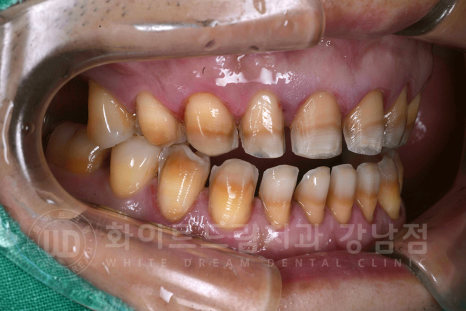

치료 전, 환자분 치아 상태.

- 어금니(37,17,16번 치아)는 현재 본원에서 UV 임플란트 치료 중입니다. ^^

강남역 인근 치과, 테트라사이클린 변색 치료 전

테트라사이클린 변색은 일반 누렁 니와 다르게 심하게 눈에 띄기에 치아 스트레스가 심하신 분들이 많습니다.

오늘 소개해 드릴 환자분도 40대의 남성분이셨는데요.

치아 변색을 한참 고민을 하다가 치료를 받기로 결심을 하신 분이었습니다.